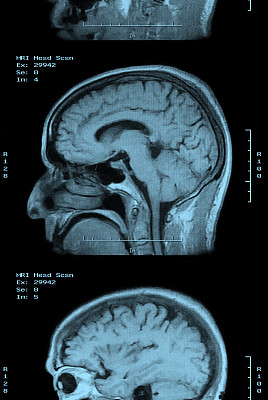

鞍结节脑膜瘤是一种发生在脑部鞍区的良性肿瘤,尽管其生长缓慢且通常不会转移,但由于其位置特殊,可能会对周围的重要神经结构造成压迫,引发一系列症状。本文旨在向读者介绍鞍结节脑膜瘤的常见症状,帮助大家更好地认识这一疾病。

鞍结节脑膜瘤虽然是良性肿瘤,但其位置特殊,可能会对患者的生活质量产生重大影响。了解其常见症状对于早期发现和治疗至关重要。一旦出现上述任何症状,应及时就医,进行专业的检查和评估。通过早期诊断和适当的治疗,大多数患者可以获得良好的预后。同时,保持健康的生活方式,如合理饮食、适量运动、保持良好的心态等,也有助于提高生活质量,减少疾病的发生风险。